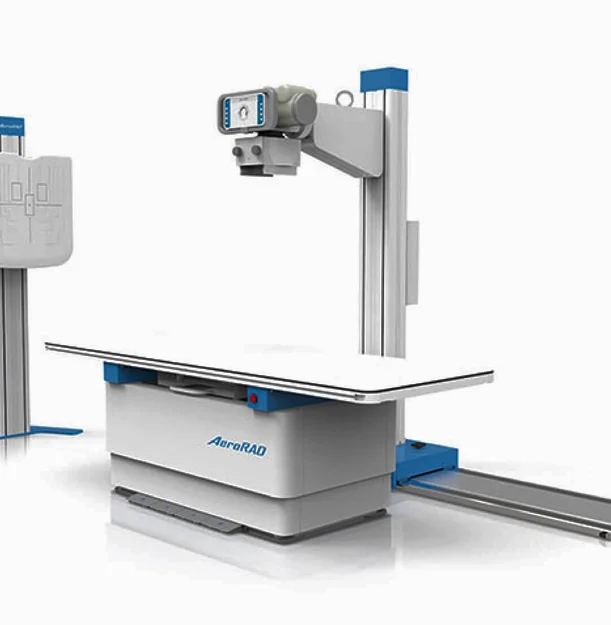

An X-ray is one of the most common and effective imaging tools used to quickly diagnose injuries and medical conditions. At Open MRI 17, our walk-in service allows you to get your X-ray done without waiting for weeks or needing an appointment. With advanced digital imaging, we provide faster scans, sharper images, and reduced radiation exposure.

Getting an X-ray is simple and comfortable. You’ll be guided by our technologists, positioned for the scan, and images will be taken in just minutes. The process is painless, quick, and ensures your doctor gets the results they need for accurate diagnosis.

In most cases, no special preparation is needed for an X-ray. However, removing jewelry, watches, or clothing with metal zippers and buttons ensures the clearest results. Our team will provide any additional instructions depending on your scan type.